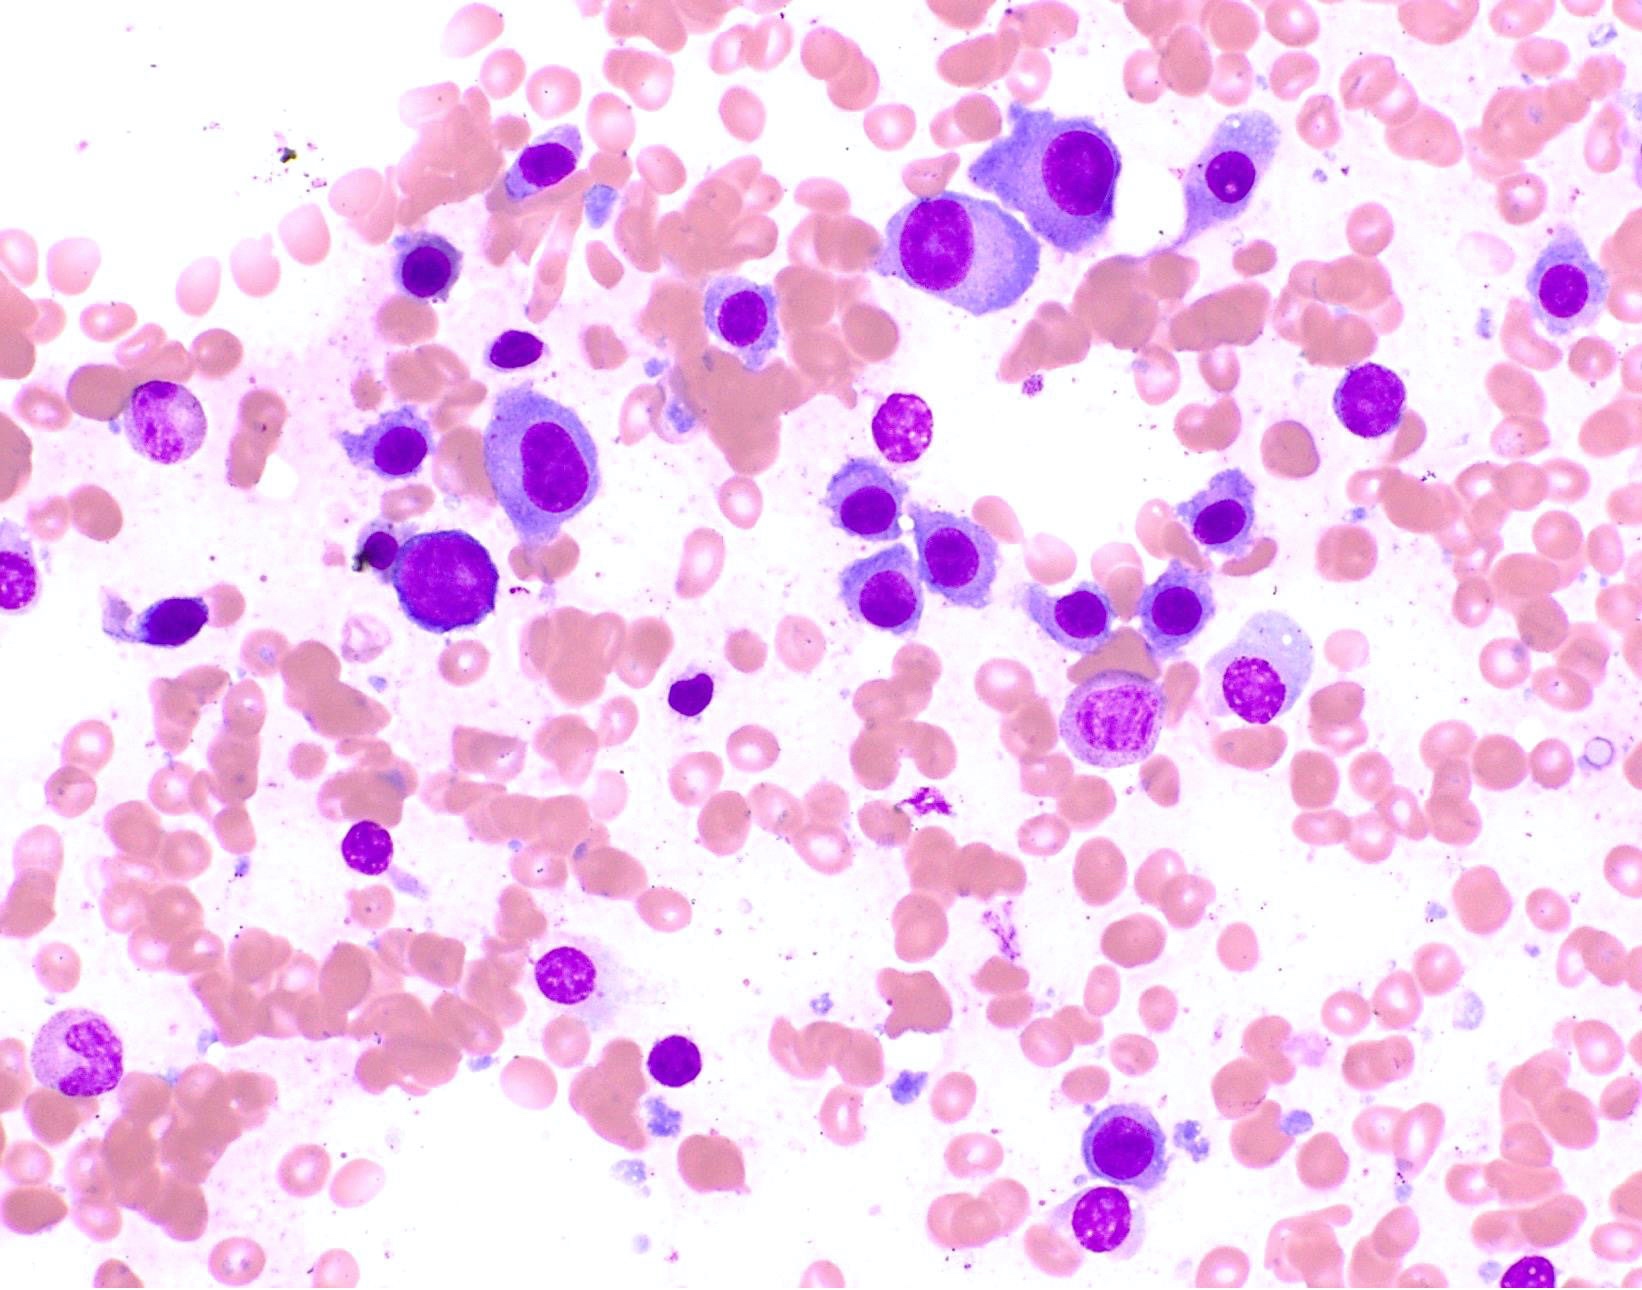

Peripheral smear description

- Rouleaux formation: erythrocytes resemble stacked coins; related to quantity and type of M protein, not specific and may be caused by alterations in other plasma proteins (Biophys J 2000;78:2470, American Society of Hematology: Rouleaux Formation [Accessed 26 May 2022])

- Leukoerythroblastic reaction can occur with extensive marrow involvement

- Circulating plasma cells can be seen in ~15% of cases, usually small numbers not meeting criteria for plasma cell leukemia (> 2 x 109/L or 20% of the leukocyte count)

Peripheral smear images